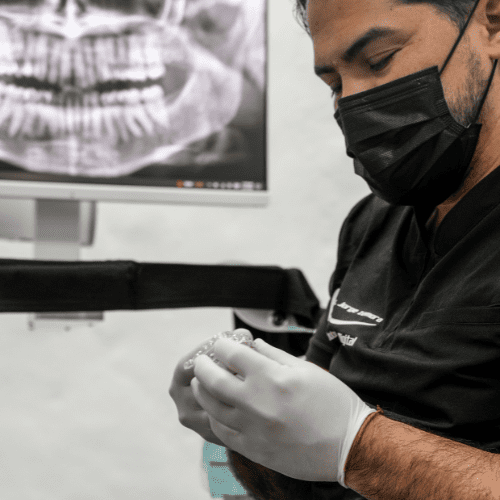

Prostodoncia hecha a la medida

En Clínica Montelimar, la prostodoncia no es una solución genérica. Es una combinación de:

- Diagnóstico estético y funcional detallado

- Materiales de última generación

- Enfoque artesanal en cada ajuste

Más allá de restaurar dientes, lo que buscamos es restaurar confianza y funcionalidad. Cada prótesis debe sentirse como parte del paciente, no como algo añadido.

Tecnología con propósito

Innovar no es tener más equipos, es tratarte mejor.

En Clínica Montelimar la tecnología existe para elevar el diagnóstico, reducir la invasión y aumentar la predictibilidad de cada tratamiento. Seleccionamos sistemas líderes del mundo que se integran a nuestro flujo clínico con un objetivo: resultados precisos y experiencias más cómodas.

Escaneo 3D sin impresiones; planificación milimétrica.

Microscopía: microcirugía con mejor preservación de tejidos.

Implantes con evidencia y perfiles estéticos naturales.

Implantes con evidencia y perfiles estéticos naturales.